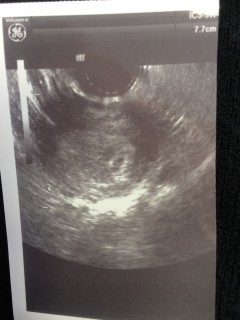

卵管にモヤがあると言われていて、子宮外妊娠を疑われていました。大きな病院で見てもらったら、ちゃんと1cmの胎嚢が確認できました!! ちゃんといてくれたことがとても嬉しい!!٩(*´꒳`*)۶やっぱり大きい病院だと間違いないと思います。二日前まで、個人病院に通っていて、まだ見えない。モヤしか見えないと言われていたのに、病院を変えたら一発で正常妊娠と言われました!次は2週間後。心拍まで確認できたらいーな☆